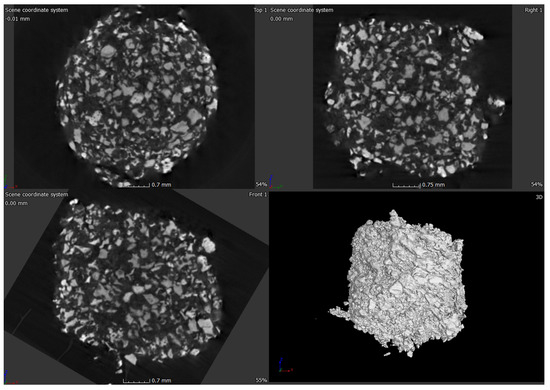

2.3. Micro-Computed Tomograpgy (μ-CT) of ABVF-BG Putty

4.5. In Vitro Antimicrobial Activity Assay